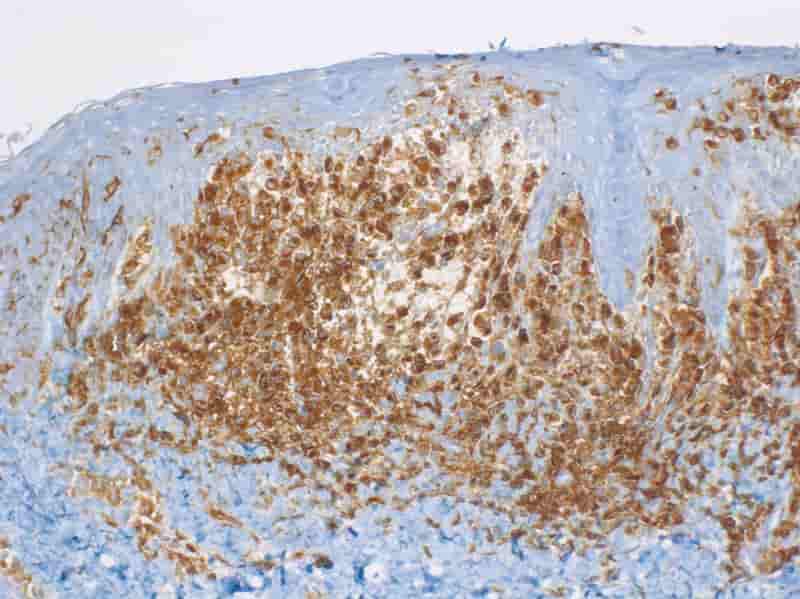

Tumor markers:

- Tumor cells express HLA-DR, S-100, CD1a. (Image below)